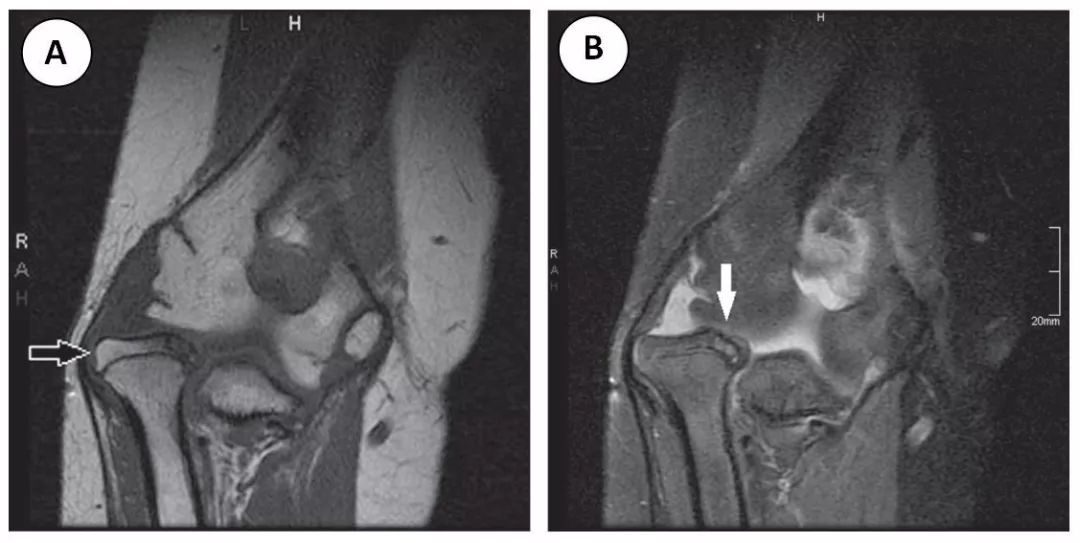

图 1 这位 14 岁的患者表现为慢性肱桡关节半脱位。冠状面 (A) TI 和 (B) PD-FS MRI 图像显示桡骨头相对于肱骨小头的颈向半脱位 (白色空箭头)。桡骨头关节软骨变薄,桡骨头骨髓信号改变 (实白色箭头),符合剥脱性骨软骨炎的特征。

图一